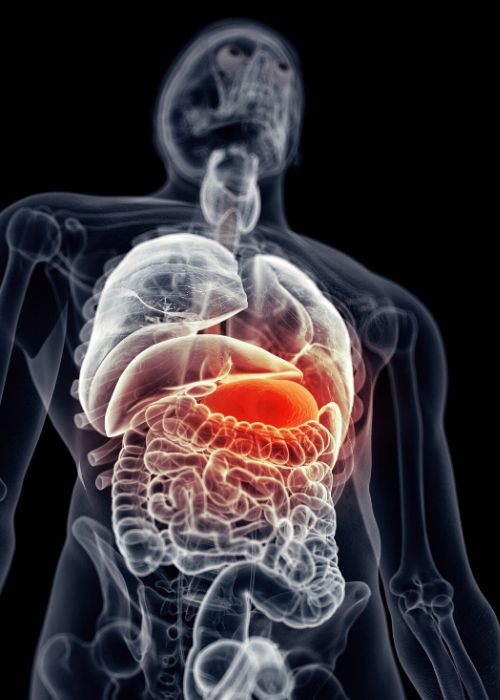

Spor yaparken ya da ağır bir fiziksel aktivite esnasında kalbiniz kaslarınıza – kan pompalar- yani kalp yoğun bir faaliyet içerisindedir. Eğer bu esnada mideniz dolu ise, kalbiniz ikinci bir faaliyete daha geçerek sindirim için midenize de kan pompalamaya başlar.

Diğer taraftan da hiçbir aktivitede bulunmasanız bile her zaman beyninize ve rutin olarak çalışmakta olan diğer iç organlarınıza da bu kanı aynı anda göndermek zorunda. Bu bir dolaşım şokudur.

Kendinizi böyle bir duruma soktuğunuzda, eğer antrenmanlı iseniz mide krampı ve tansiyon oynaması gibi hafif sonuçlarla kurtulursunuz, ama antrenmansız ya da düzensiz antrenman yapan biriyseniz, hele orta yaş ve üzerinde iseniz kalp krizi geçirme riskiniz çok olasıdır.

Dolu mide ile spor yapmak kalbinize adeta sırtınızda başka bir adamı taşırken spor yapmanızla eş değer bir yorgunluk yükler. Aslında bu durum mideniz dolu iken yaptığınız her türlü fiziksel aktivite için geçerlidir. Sadece aktivitenin ağırlığına göre risk oranları değişebilir.

Çünkü, insan vücudundaki tüm aktiviteler kan dolaşımıyla ilgilidir. Beyin de dahil tüm organlara bu kanı pompalayan motor ise kalbinizdir.